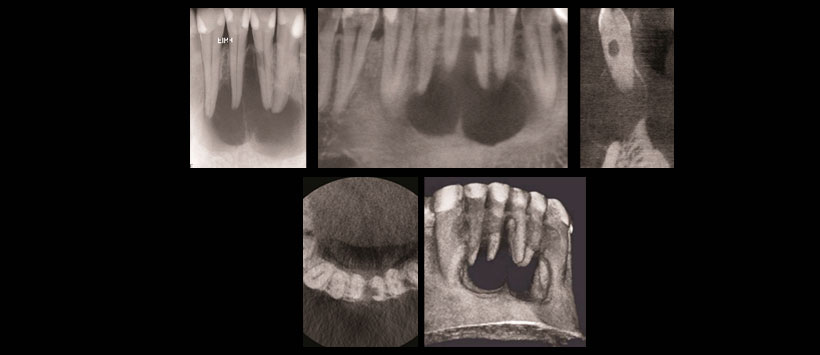

Figura 1: Tomografía volumétrica de haz cónico para la evaluación de resorción radicular interna y patología apical.

- Patología periapical (Figura 1)

- Reabsorciones radiculares (Figura 1)